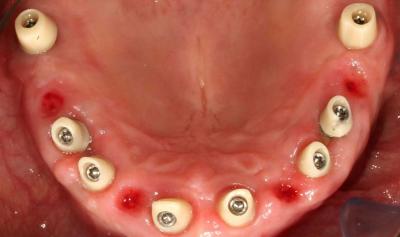

Фото 1. Назначают полоскания, которые необходимо держать в ротовой полости минимум в течение одной минуты.